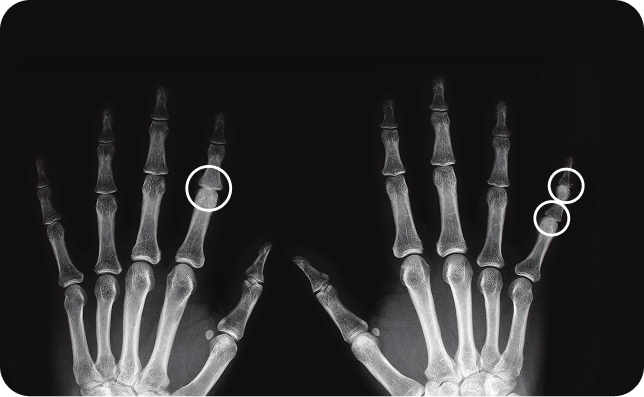

This 24-week randomized, double-blind, placebo-controlled, parallel-group, multicenter, phase 3b study was conducted according to the ethical principles of the Declaration of Helsinki and Good Clinical Practice.

Patients received Cosentyx 300 mg or placebo at baseline, weeks 1, 2, and 3, and then every 4 weeks from week 4 to 20. The final efficacy and safety evaluations were performed at week 24.5

Placebo-treated patients who achieved a PSSI improvement of 90% (PSSI 90) response at week 12 continued receiving placebo, and those who did not achieve a PSSI 90 response at week 12 switched to treatment with Cosentyx 300 mg at weeks 12, 13, 14, 15, 16, and 20.5

The primary objective was to determine the proportion of patients using Cosentyx 300 mg or patients using placebo who achieve a PSSI 90 score at week 12.

At week 12, PSSI 90 was achieved by 52.9% of patients receiving secukinumab 300 mg and by 2.0% of patients receiving placebo (difference between proportions: 0.51, 95% CI 0.37-0.65, P <.001)5

*(HR 3.89, 95% CI 2.18 – 6.94) compared with those without scalp lesions

†Mean baseline PSSI score was 33.5

PsA=psoriatic arthritis; PSSI=Psoriasis Scalp Severity Index; NRI=nonresponder imputation; QW=every week; Q4W=every 4 weeks.